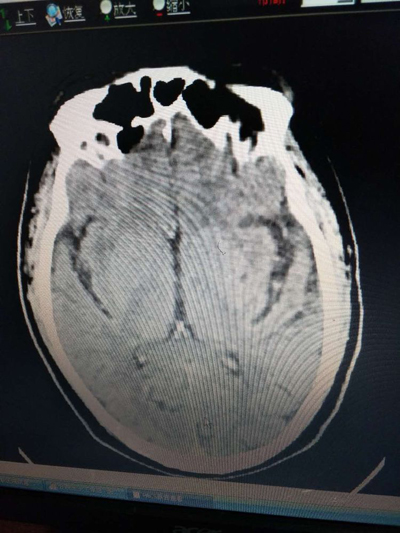

溶栓前头部CT,排除脑出血

立即请神内会诊,神内非常重视该患者,迅速做完评估,头颅CT未见梗死及出血,患者无静脉溶栓禁忌症,跟家属谈话对溶栓风险表示理解,立即启动尿激酶静脉溶栓,患者于两个半小时后神志恢复,未留后遗症。